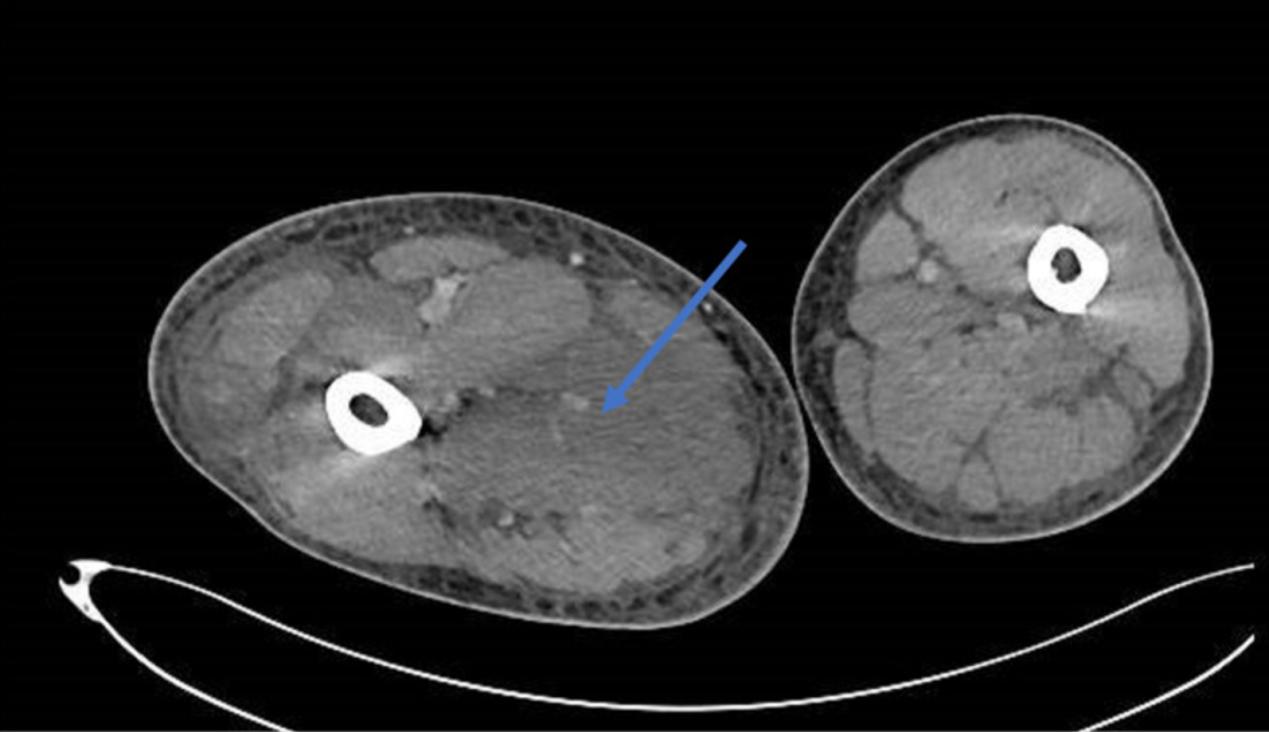

初步检查包括排除深静脉血栓形成的多普勒超声评估。右大腿的计算机断层扫描显示了肌炎,软组织水肿累及肌肉平面,尤其是内收肌(图1)。

图1